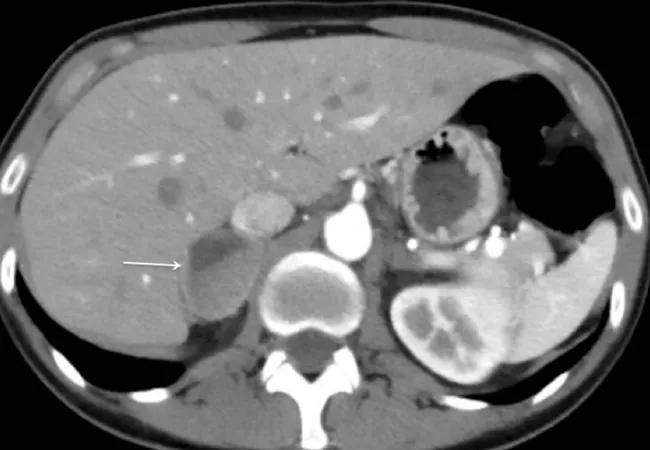

While many tumors of the adrenal gland are noncancerous, they can cause life-threatening disease due to an overproduction of “fight-or-flight” hormones. One such tumor type is called pheochromocytoma.

Pheochromocytomas are complex catecholamine-secreting tumors of the adrenal medulla with an annual incidence of two to eight cases per million. They affect the medulla and cause an overproduction of adrenaline, which can lead to hypertension, profuse sweating, headaches, panic attacks, arrhythmia, stroke and even death. Many of the tumors are sporadic in nature, while at least half are associated with a genetic disorder. Patients with disease-causing gene mutations are at higher risk for developing subsequent tumors.